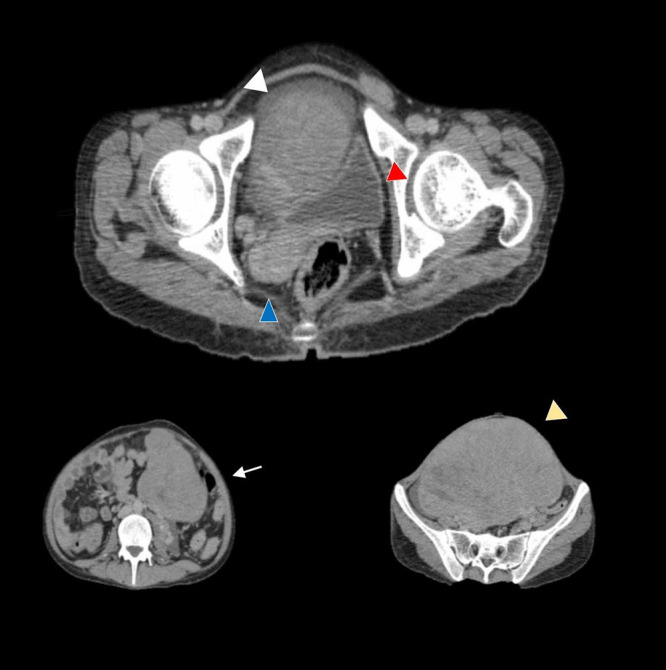

Case presentation: We present the case of a 22-year-old male who presented with abdominal pain and distension. Upon physical examination, he exhibited characteristics consistent with ambiguous genitalia, including a small penis and an absent scrotal sac. The diagnostic imaging, particularly computed tomography (CT) scans, revealed a large solid mass in the left adnexa. This mass displayed lobulated outlines and speckled calcifications, which raised concerns for a potentially malignant process. Given the findings, the patient underwent surgical intervention, which included a total abdominal hysterectomy, bilateral salpingo-oophorectomy, and omentectomy to ensure complete removal of the tumor and surrounding affected tissues. Histopathological analysis of the excised tissue confirmed the diagnosis of dysgerminoma, a type of germ cell tumor known for its malignant potential.